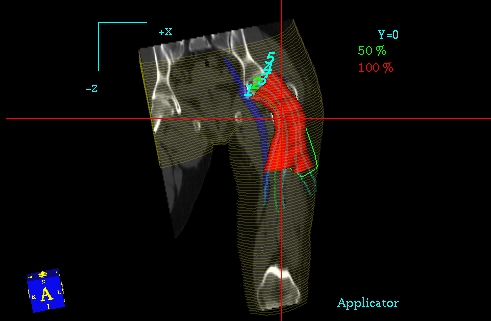

Planowanie 3D PLATO - przekrój czołowy, widoczny CTV, rozkład izodoz

Planowanie 3D PLATO - przekrój strzałkowy, widoczny CTV, rozkład izodoz